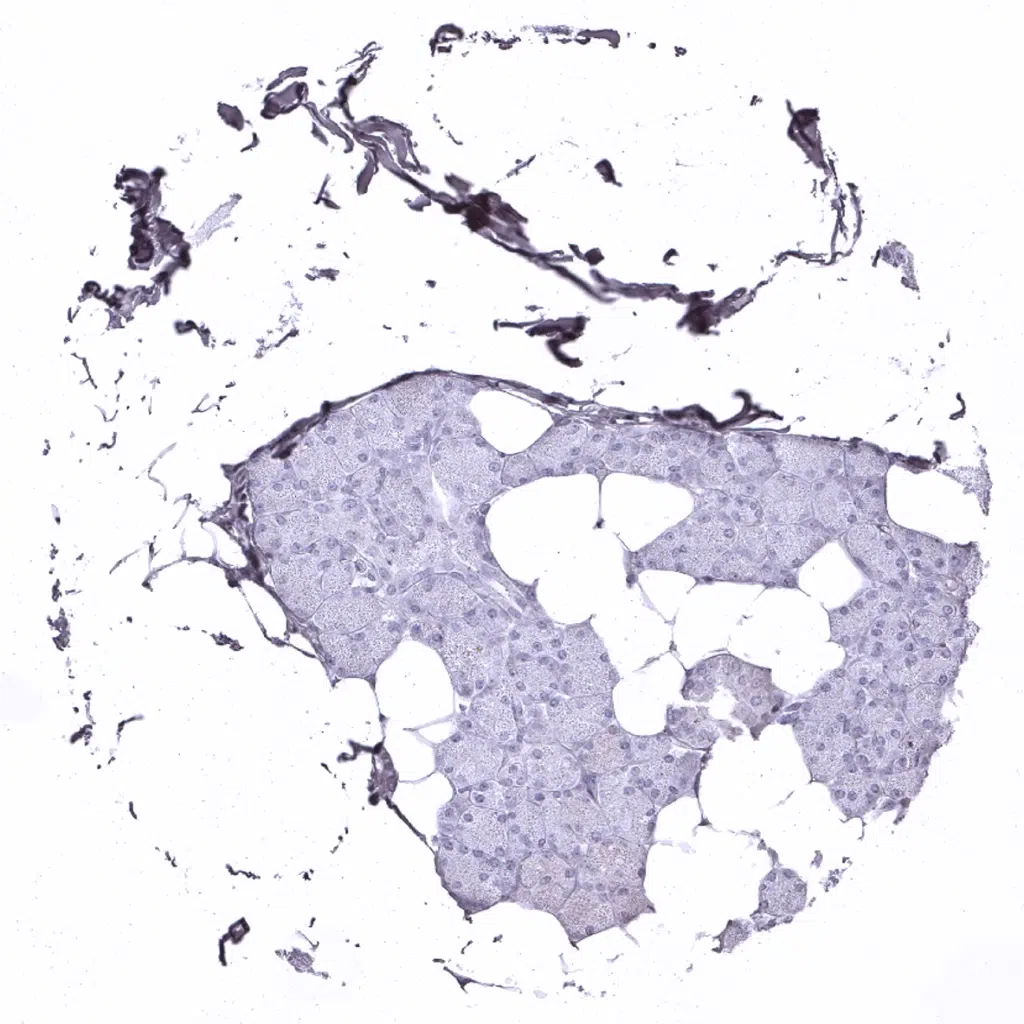

Pancreas